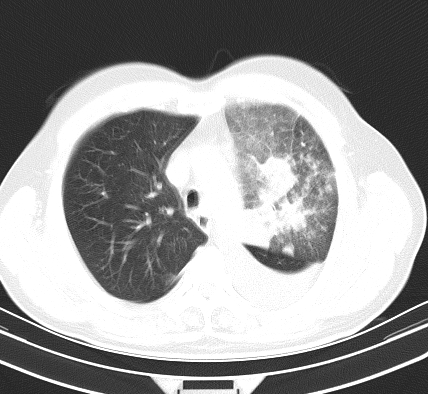

以下是引用老爱克斯新网客在2008-7-31 6:30:00的发言:[br]左肺上叶大片状病灶,左肺上叶支气管狭窄呈鼠尾状,左肺门增大,纵隔内见肿大淋巴结,左侧胸腔积液,余肺清晰。左肺中心型肺癌淋巴结转移,

以下是引用zjb在2008-7-31 6:32:00的发言:[br]左侧中心性肺癌 阻塞性肺炎 肺不张 胸腔积液 建议气管镜

以下是引用zjzjr在2008-7-31 8:45:00的发言:[br]考虑左侧中心性肺癌伴阻塞性肺炎,左肺上叶肺不张,纵隔淋巴结转移;左侧胸腔积液。建议行纤支镜检查。

以下是引用sdzyy在2008-7-31 8:47:00的发言:[br]病灶较治疗前有所进展,胸水增多, 左侧中心性肺癌 并 阻塞性肺炎 肺不张 胸腔积液 可能性大; 建议气管镜检查。 [br] [br]